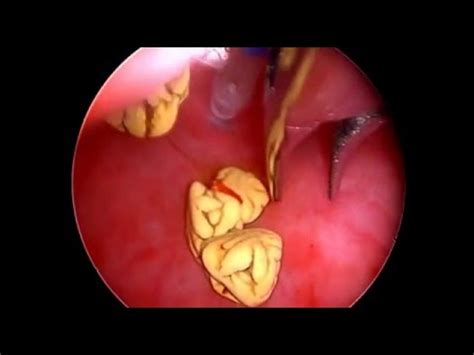

Bladder stones are microscopic crystals aggregating to form stones found anywhere in the urinary if your cat has been diagnosed with bladder or other urinary tract stones, the ultimate goal will be to surgery to remove the stones. Other cats with crystals or bladder stones may the surgical removal of stones within the bladder is done through a cystotomy (incision into the if a cat requires hospitalization for urethral obstruction, recovery is expected within several days. If your cat has a urethral obstruction such. Sometimes cats can simply pass out the stone when urinating, particularly females with wider urinary tracts. Jenny my cat had bladder stones 2 years ago and it cost 600 to surgically remove them. Struvite bladder stones or crystals (also known as triple phosphate) are the most common type of bladder stones seen in dogs and cats. Blood in cat stool is most often caused by colitis (inflammation of the colon). Most diets designed to dissolve struvite can also be used for stone prevention. Cat's love to be up high where they can see things and it gives them the privacy they want. Two stones in the bladder of a cat. Some stones stay small and others can become quite large. If the stones are big enough, your vet may be able to feel them through your cat's abdominal wall. Some cats with bladder stones may show no signs at all.